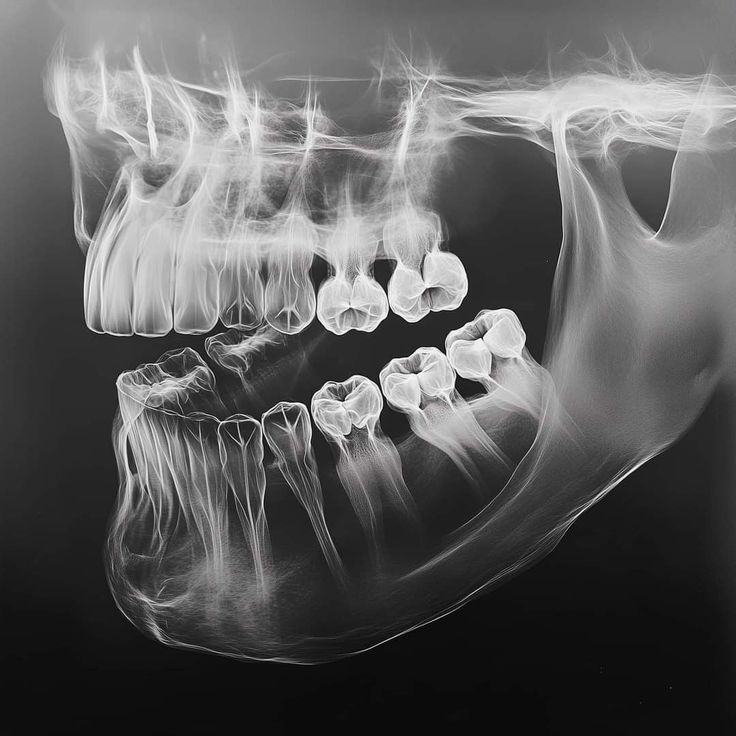

cirugía alveolar

(Extracciones dentales)

Incluye todo los procedimientos o técnicas quirúrgicas que involucren al hueso maxilar y mandíbula, los dientes y sus tejidos de soporte como extracciones dentales / terceros molares (cordales).

¿qué exámenes se requieren?

Extracciones dentales:

• Radiografía Panorámica